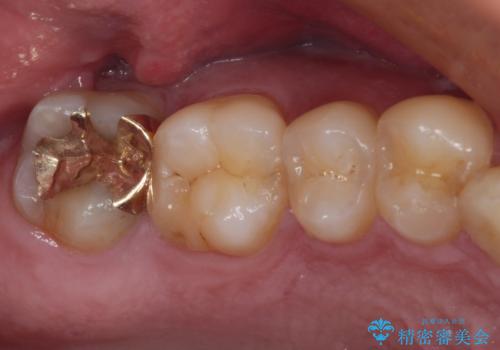

非常に咬合力が強く、銀歯やセラミックのような堅い素材では歯にダメージがかかり、治療を繰り返す可能性が高いと思われたので、ゴールドインレー(白金加金インレー、PGAインレー)にて、治療中の歯と銀歯が装着されている歯を修復治療することとしました。

ゴールドインレーは銀歯のインレーやセラミックインレーと比べ、「技工操作の精度が高く、適合が著しく良い」というメリットがあります。特に上の奥歯は歯科医師の操作が行いにくいため、「適合の良さ」は再治療のリスクを防ぐ上でとても重要な要素となります。

上の奥歯は金属色が見えることもないため、審美的な問題は全くありません。